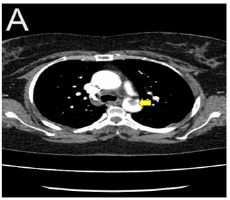

Case Report

Stanford Type A Aortic Dissection Complicated by Rupture in to the Pericardium a Case Report